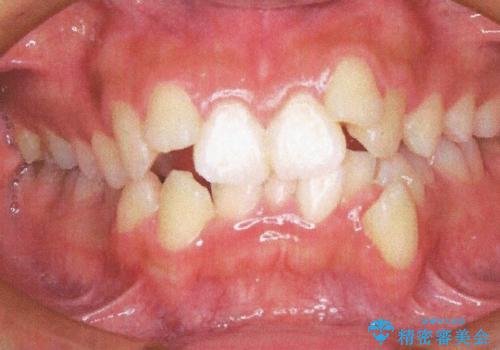

前歯が八重歯でガタガタ ワイヤーによる抜歯矯正